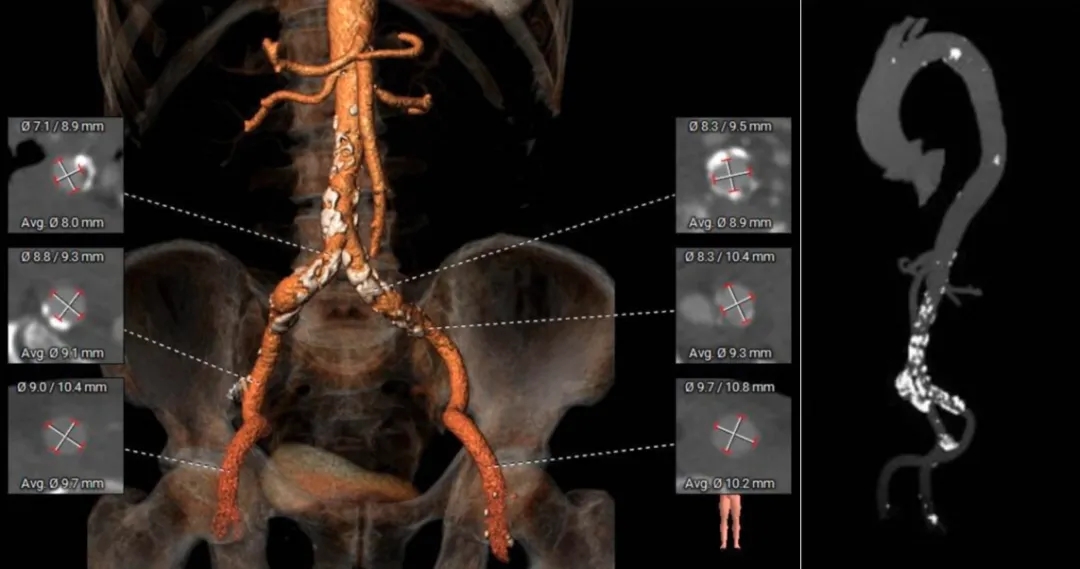

术前CT分析

主动脉根部测量

ANNULUS

LVOT

SOV DIAMETER

周长75.7mm

周长径24.4mm

周长83.2mm

周长径26.5mm

内径

31.6*38.6*36.5mm

STJ

ASCENDING

AORTA

心脏角度

周长107.2mm

周长径34.1mm

周长116.2mm

周长径37mm

心脏角度:58°

瓣上结构测量

SUPRA-2MM

SUPRA-4MM

周长76.4mm

周长径24.3mm

周长77.5mm

周长径24.7mm

SUPRA-6MM

SUPRA-8MM

周长83.4mm

周长径26.6mm

周长86.4mm

周长径27.5mm

根部整体锚定空间有限,瓣膜锚定难度大。

冠脉风险评估

Left Coronary 8.0mm

Right Coronary 18.7mm

LCA & Leaflet

RCA & Leaflet

Left Ventricular

-

左冠开口低,结合瓦氏窦大小,存在冠脉风险

收缩期大左室,典型关闭不全引起的心室扩张

外周入路评估

血管轻微迂曲

腹主可见钙化斑块

主动脉弓平缓